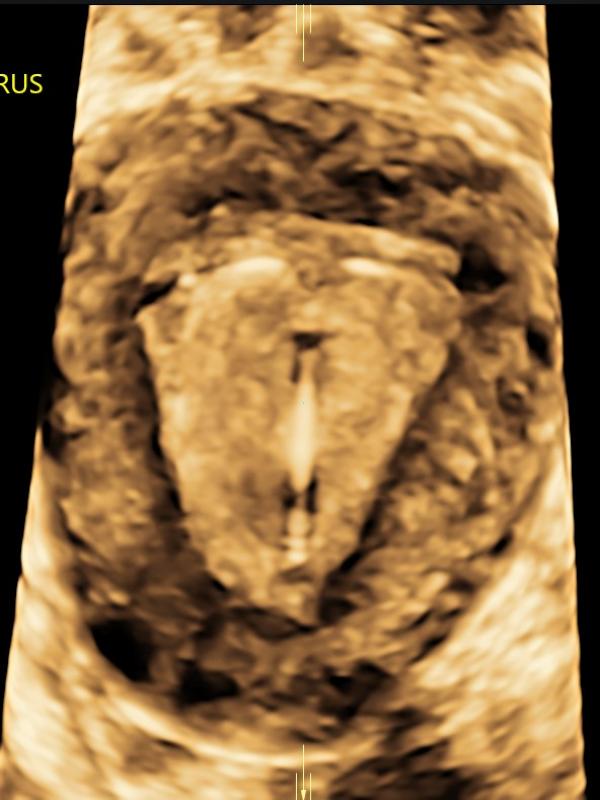

• 3D/4D Ultrasounds: The best time in the pregnancy for 3D/4D imaging is between 26 and 30 weeks gestational age. At this time there is plenty of amniotic fluid around the baby. Fluid enhances the images and adequate amniotic fluid around the baby is essential for good 3D/4D imaging. As the baby gets closer to term the amniotic fluid naturally decreases, making it more difficult to get good 3D/4D images. Also, 26-30 weeks is a good time for the 3D/4D because the baby has started to “fill out” and take on some of the features it will have at birth. Before 26-30 weeks gestational age the baby looks more skeleton-like. There are a number of factors that affect the quality of the 3D/4D images. Ideally, the baby is positioned away from the placenta and uterine wall. If the fetal hands, feet or umbilical cord are in front of the face it will result in less than ideal images. In order to have a 3D/4D ultrasound at Sound Health Imaging you must have a referral from your medical provider. During the 3D/4D ultrasound, measurements will be taken to assess fetal growth, but an anatomical survey of the baby will not be done. We require that a previous 20-22 week ultrasound for fetal anatomical surveillance has already been done prior to the 3D/4D ultrasound. 3D/4D ultrasounds are not medically necessary and cannot be billed out to insurance companies. Please contact our office for more information.